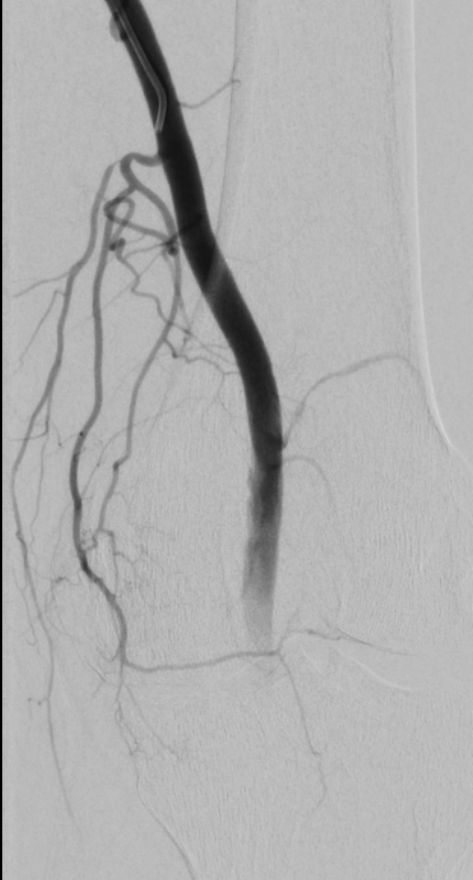

GAE - interesting variant - looks like the superomedial genicular artery is arising the the descending GA as a variant. Haven't run into this before.